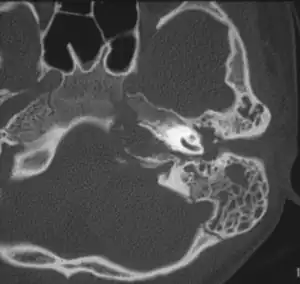

| Apicitis petrosa as seen in computed tomography | |

In persons with longstanding ear infection and typical symptoms, medical imaging such as CT or MRI of the head may show changes that confirm disease involvement of the petrous apex of temporal bone.